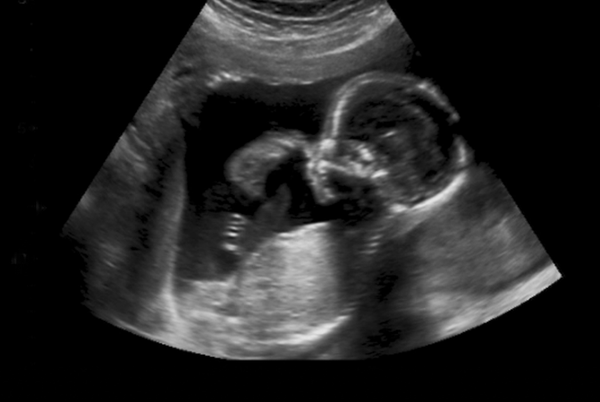

Yolande sits quietly in our office, tears welling up in her eyes. Her eight-month-old baby has been really sick, but she fears going to the hospital only to be turned away. Yolande is an asylum seeker in South Africa. She is currently enrolled in JRS’ livelihoods program and lives with her husband and two other children.

Yolande gave birth to Divine at a public hospital in Pretoria. Unfortunately, Yolande had health complications related to the delivery and remained in hospital for several weeks. She was not informed of the new policy being implemented at public hospitals regarding maternity services for foreign patients. On discharge, she was told to pay R120000 for the delivery and in-patient services—an

In the last few weeks, Divine has been sickly and struggled with breathing. Yolande has saved up money to take him to a private doctor, but this is untenable. She is worried about going to the public hospital and being turned away or told to pay more money.